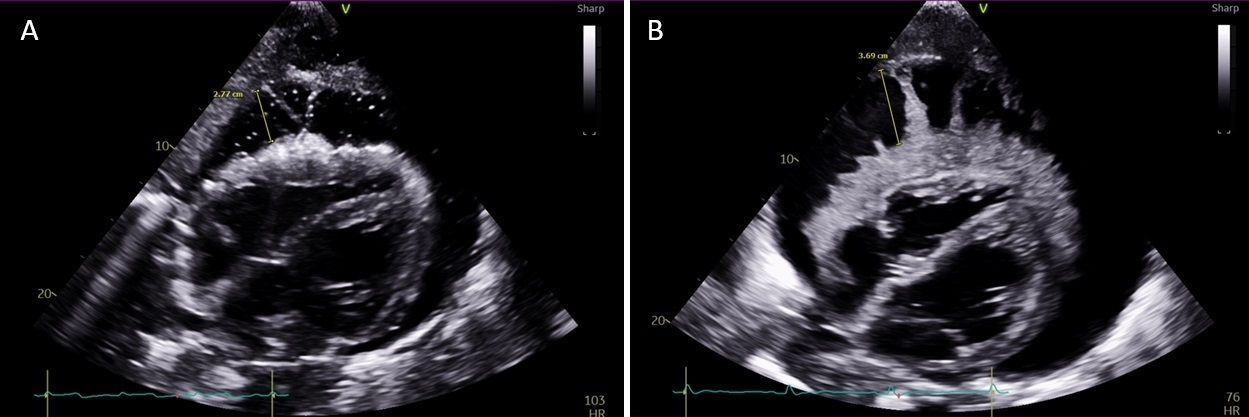

A 36-year-old male with methamphetamine-induced heart failure, esophageal stricture, cachexia, and esophageal candidiasis presented with chest pain after blunt chest trauma. Chest CT showed multifocal pneumonia and a large pericardial effusion with pneumopericardium. TTE revealed a loculated pericardial effusion without tamponade and a thick epicardial rind (Fig. 1A). Pericardiocentesis yielded 40 mL of yellow, gelatinous, acellular fluid.

Later in the admission, he became hypotensive requiring vasopressors. Repeat TTE showed a very large effusion with tamponade physiology and new fingerlike tendrils on the epicardial surface (Fig. 1B). He was transferred for urgent pericardiocentesis with removal of 1.4 L of turbid, yellow-opaque fluid resulting in hemodynamic improvement (Fig. 2). Initial fluid studies were non-diagnostic and sterile. However, culture eventually grew Candida albicans and he began treatment with micafungin.